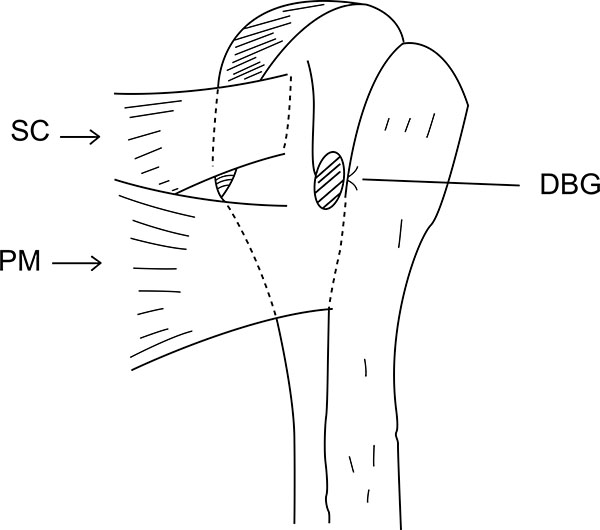

Using a proximal delto-pectoral skin incision, the distal part of the bicipital groove (DBG) is exposed, retracting the deltoid-pectoral complex superolaterally with a Hohmann retractor, while the short head of the biceps brachii and the coracobrachialis muscles are retracted medially with a right angled retractor. Adequate visualization of the distal part of the biceps groove is paramount. One should avoid vigorous medial retraction to protect the musculocutaneous nerve. The site for drilling is identified at the distal-most aspect of the biceps groove (Fig. 2).

At this stage, we go back to our first incision site to prepare the tenodesis site. The distal part of the bicipital groove (DBG) is identified and cleared off soft tissues. A 2.7mmx 15” guide wire is drilled at an angle of 45º through the center of DBG. Care should be taken to avoid skydiving off the edge of the humeral shaft (Fig. 3B). The guide wire should be stopped as soon as the pin penetrates the posterior cortex (Fig. 4A). This is followed by drilling the anterior cortex over the guide wire with a calibrated cannulated drill, the size of which is the same as the measured diameter of the tendon (in our case, a 7-mm drill for a 7-mm tendon) (Figs. 3C, 4B). Care is taken to only drill up to the posterior cortex without engaging the cortex or plunging through. Depth of this bone tunnel is measured with the aid of a calibrated drill (TD- Tunnel Depth). Usually it is around a 20-25mm tunnel in adults. The hole should be lined up at the base of the biceps groove and cleared of soft tissue. Finally, the posterior cortex is drilled through with a 4.5-mm drill to allow for the passage of the cortical button (Fig. 4C).